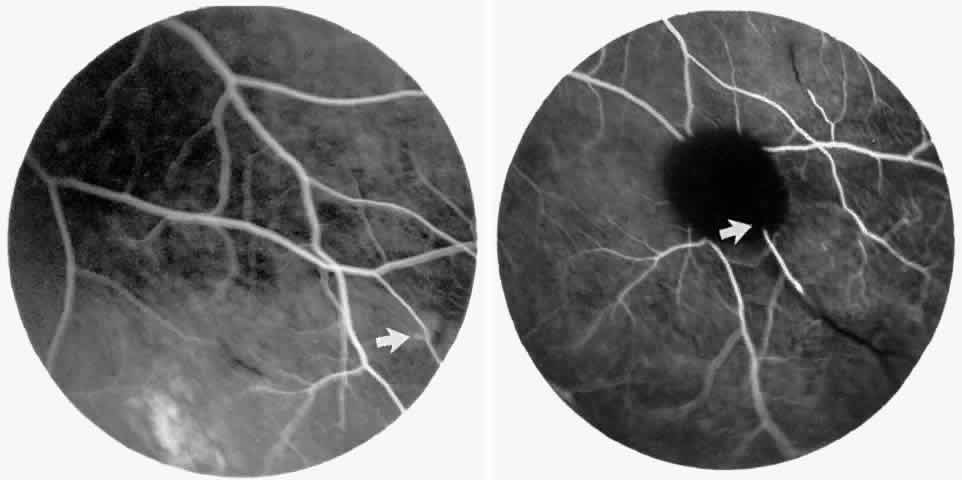

Macular Function Testing in Sickle

Cell MaculopathyThe visual acuity in patients with sickle cell disease is often normal, despite the presence of an enlarged foveal avascular zone or other evidence of sickle cell maculopathy (Fig. 14). In addition, patients with sickle cell maculopathy have a remarkable absence of visual complaints. Although 55% of patients with homozygous sickle cell anemia had abnormal contrast sensitivity, no significant relationship was demonstrated between contrast sensitivity and macular vascular abnormalities.101 Automated visual field analysis has demonstrated significantly larger scotomas in patients with abnormally enlarged foveal avascular zone.102 Color vision testing has revealed a greater incidence of blue-yellow defects in patients with sickle cell retinopathy; however, no significant correlation has been demonstrated between color vision defects and the presence of sickle cell maculopathy.98,107

Fig. 14. A 25-year-old woman with Hb S-β-thalassemia and bilateral proliferative sickle retinopathy (visual acuity 20/25 OD and 20/15 OS). A. Photograph of the right eye demonstrates an irregular macular reflex believed to represent a macular depression sign. B and C. Fluorescein angiogram shows loss of capillary filling corresponding to the area of irregular reflex. D. Octopus perimetry of the right eye shows a large nasal visual field defect corresponding to the area of retinal nonperfusion. E. Photograph of the left eye demonstrates an irregular retinal reflex from the temporal macula, believed to represent a retinal depression sign. F. Fluorescein angiogram shows loss of capillary filling corresponding to the area of irregular reflex. G. Octopus perimetry of the left eye shows a scotoma corresponding to the area of nonperfusion. H. Contrast sensitivity test demonstrates decreased high spatial frequency thresholds (O—O = OD, X- - -X = OS).